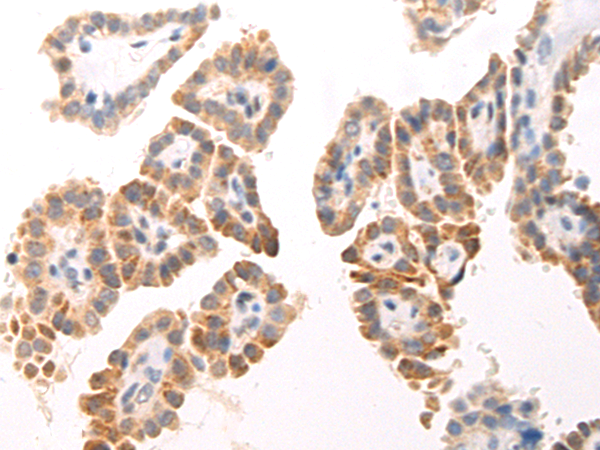

分类: 科研抗体货号: P00237别名: CPSB, ACC-4, ACC-5, minichain应用: WB,IHC反应种属: Human, Mouse, Rat